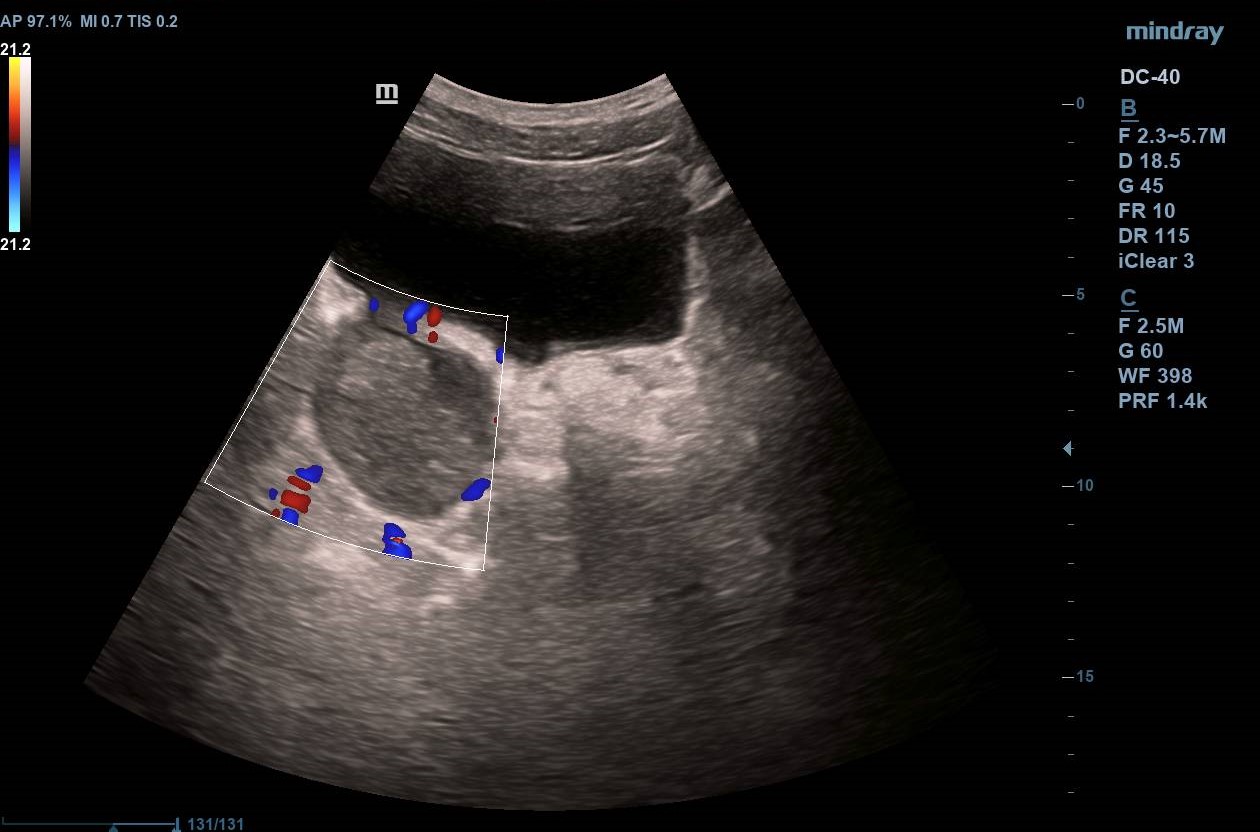

Divertículo vesical de 6 cm de diámetro en cuyo interior se observa masa homogénea de 4,43 x 3,15 cm que no capta Doppler y que parece depender de pared diverticular. Próstata homogénea de 37 cm3 (Imagen 1).